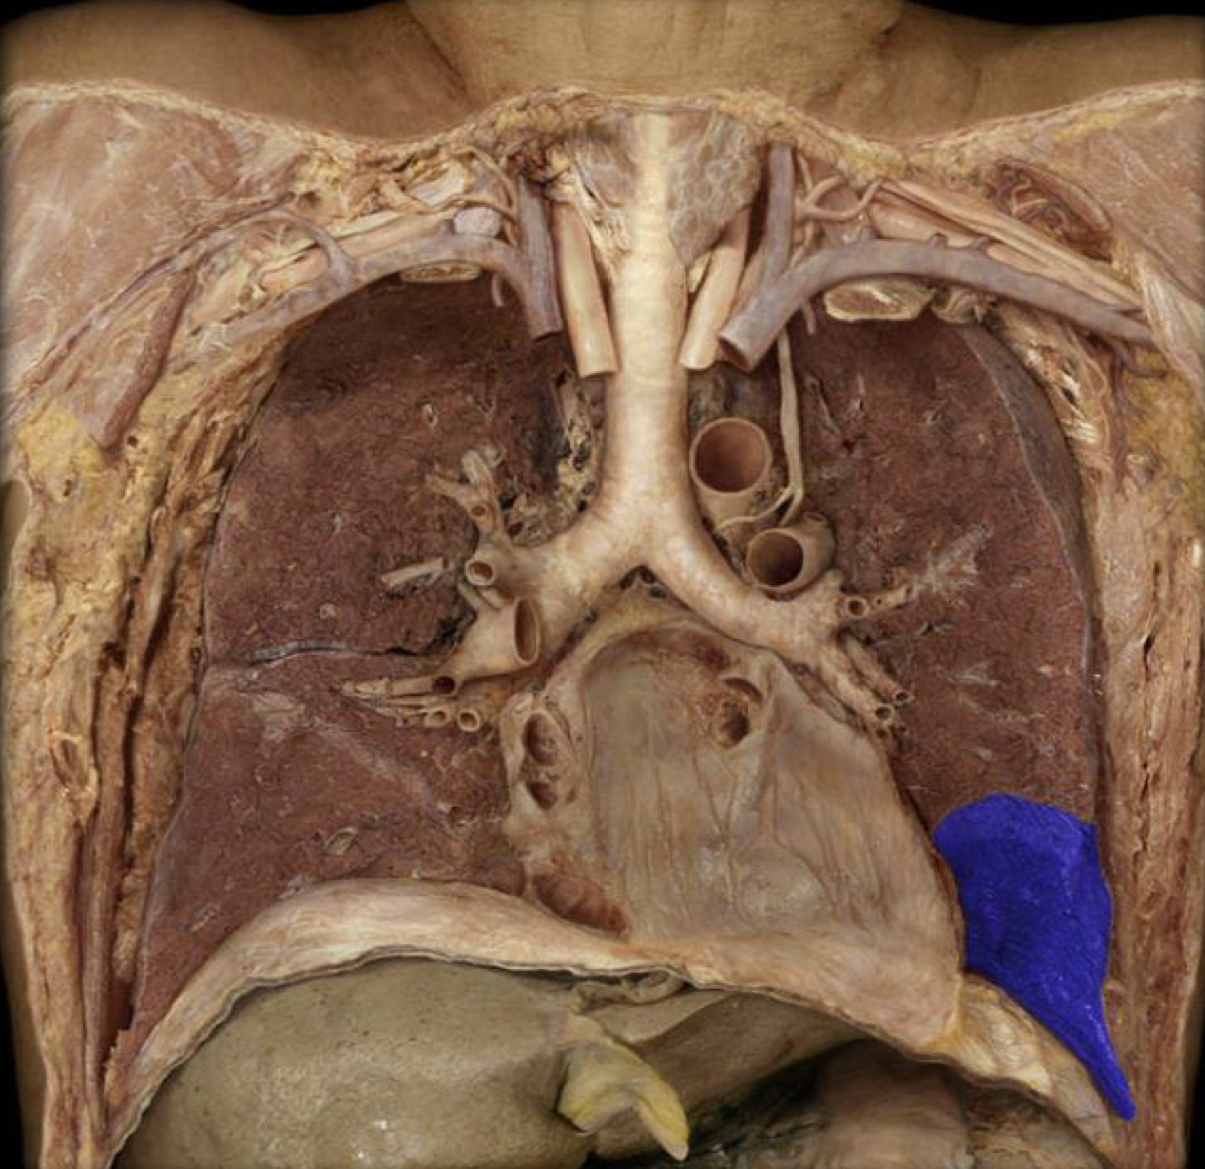

What structure is highlighted in blue?

Hilum

New cards

Lung

Mediastinal pleura

Cervical pleura